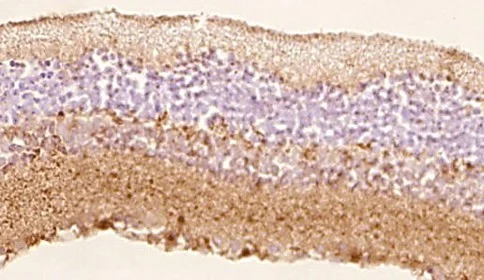

Гистологические методы оценки изменений сетчатки и зрительного нерва